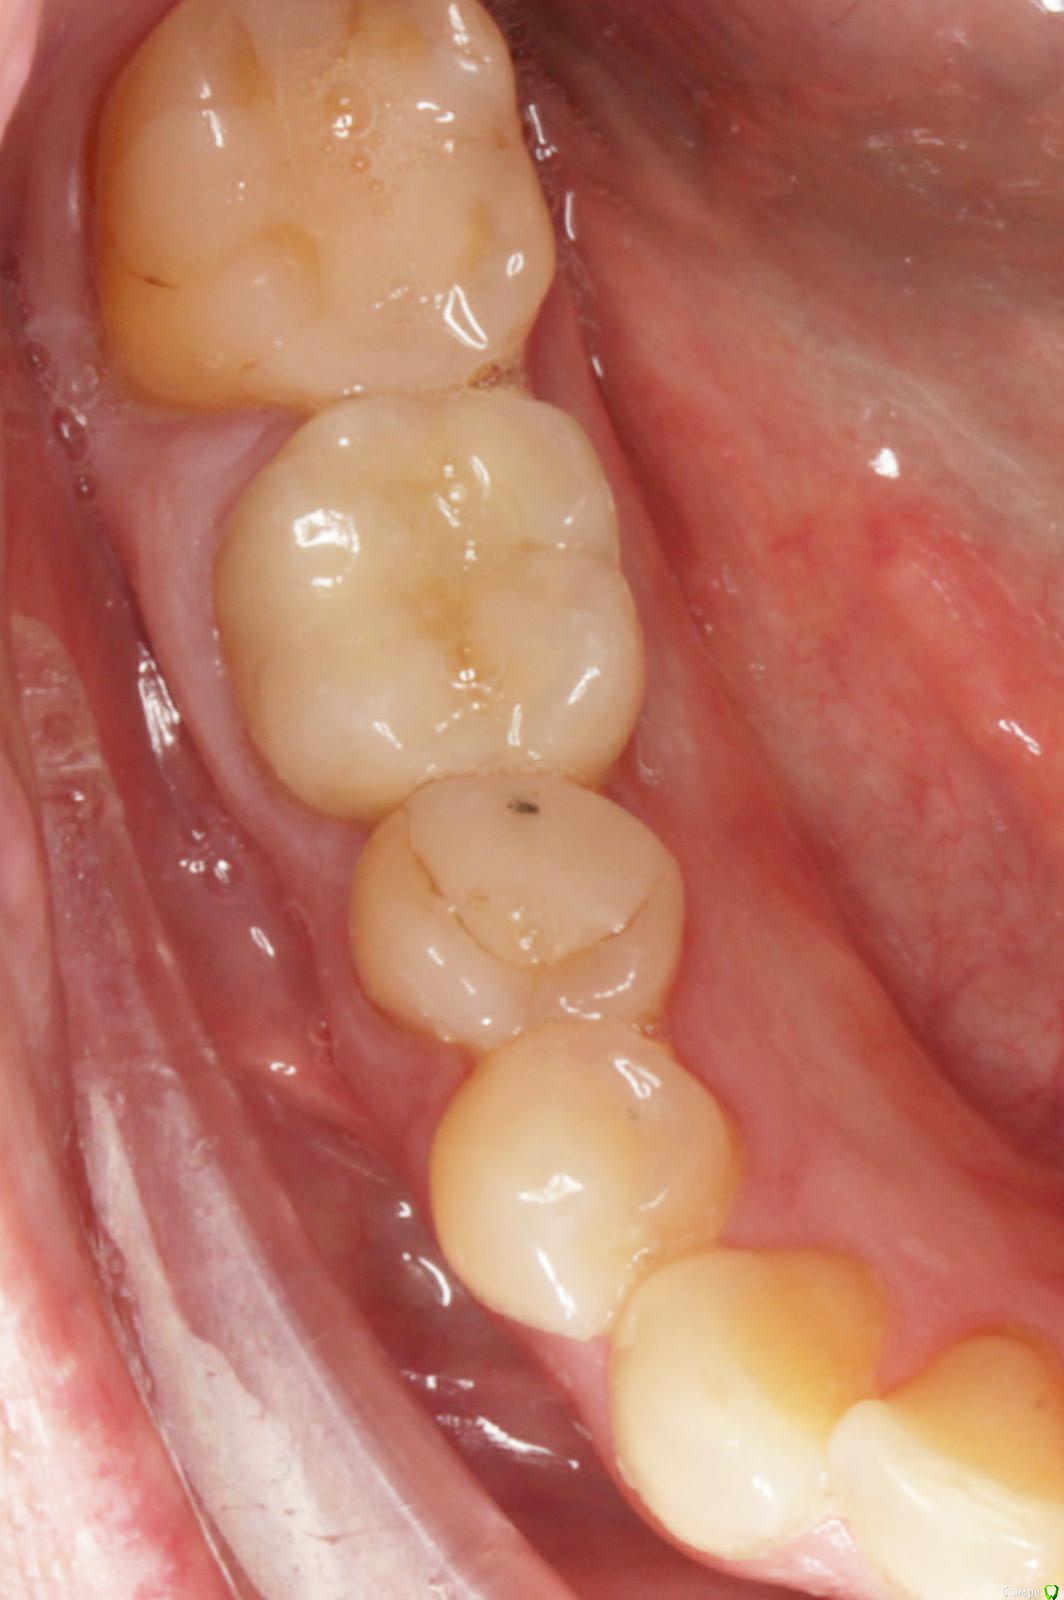

Dmitry DK Опубликовано 29 августа, 2019 Поделиться Опубликовано 29 августа, 2019 Добрый день всем! Случай достаточно заурядный, но возможно кому-то будет интересно. Результат - 2 года спустя 13 Ссылка на комментарий

Dmitry DK Опубликовано 18 сентября, 2019 Автор Поделиться Опубликовано 18 сентября, 2019 какая фиксация?Винтовая 1 Ссылка на комментарий